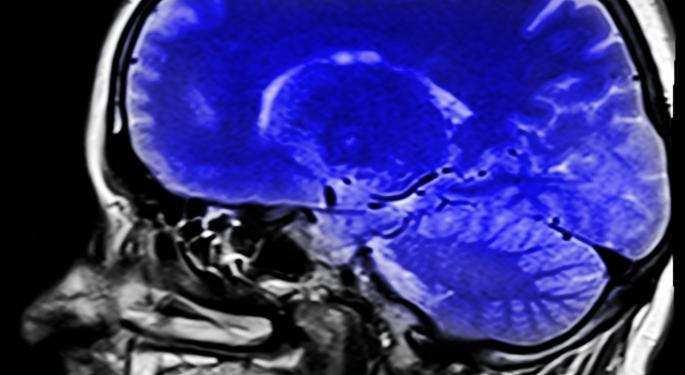

Analyst David Nierengarten explained that Voyager Therapeutics has selected various Central Nervous System (CNS) diseases, “with validated, specific gene targets that are amenable to AAV gene therapy.”

The CNS is an “ideal site for gene therapy due to its “immune privilege” status and terminally-differentiated cells that allow long-term transgene expression,” Nierengarten went on to say.